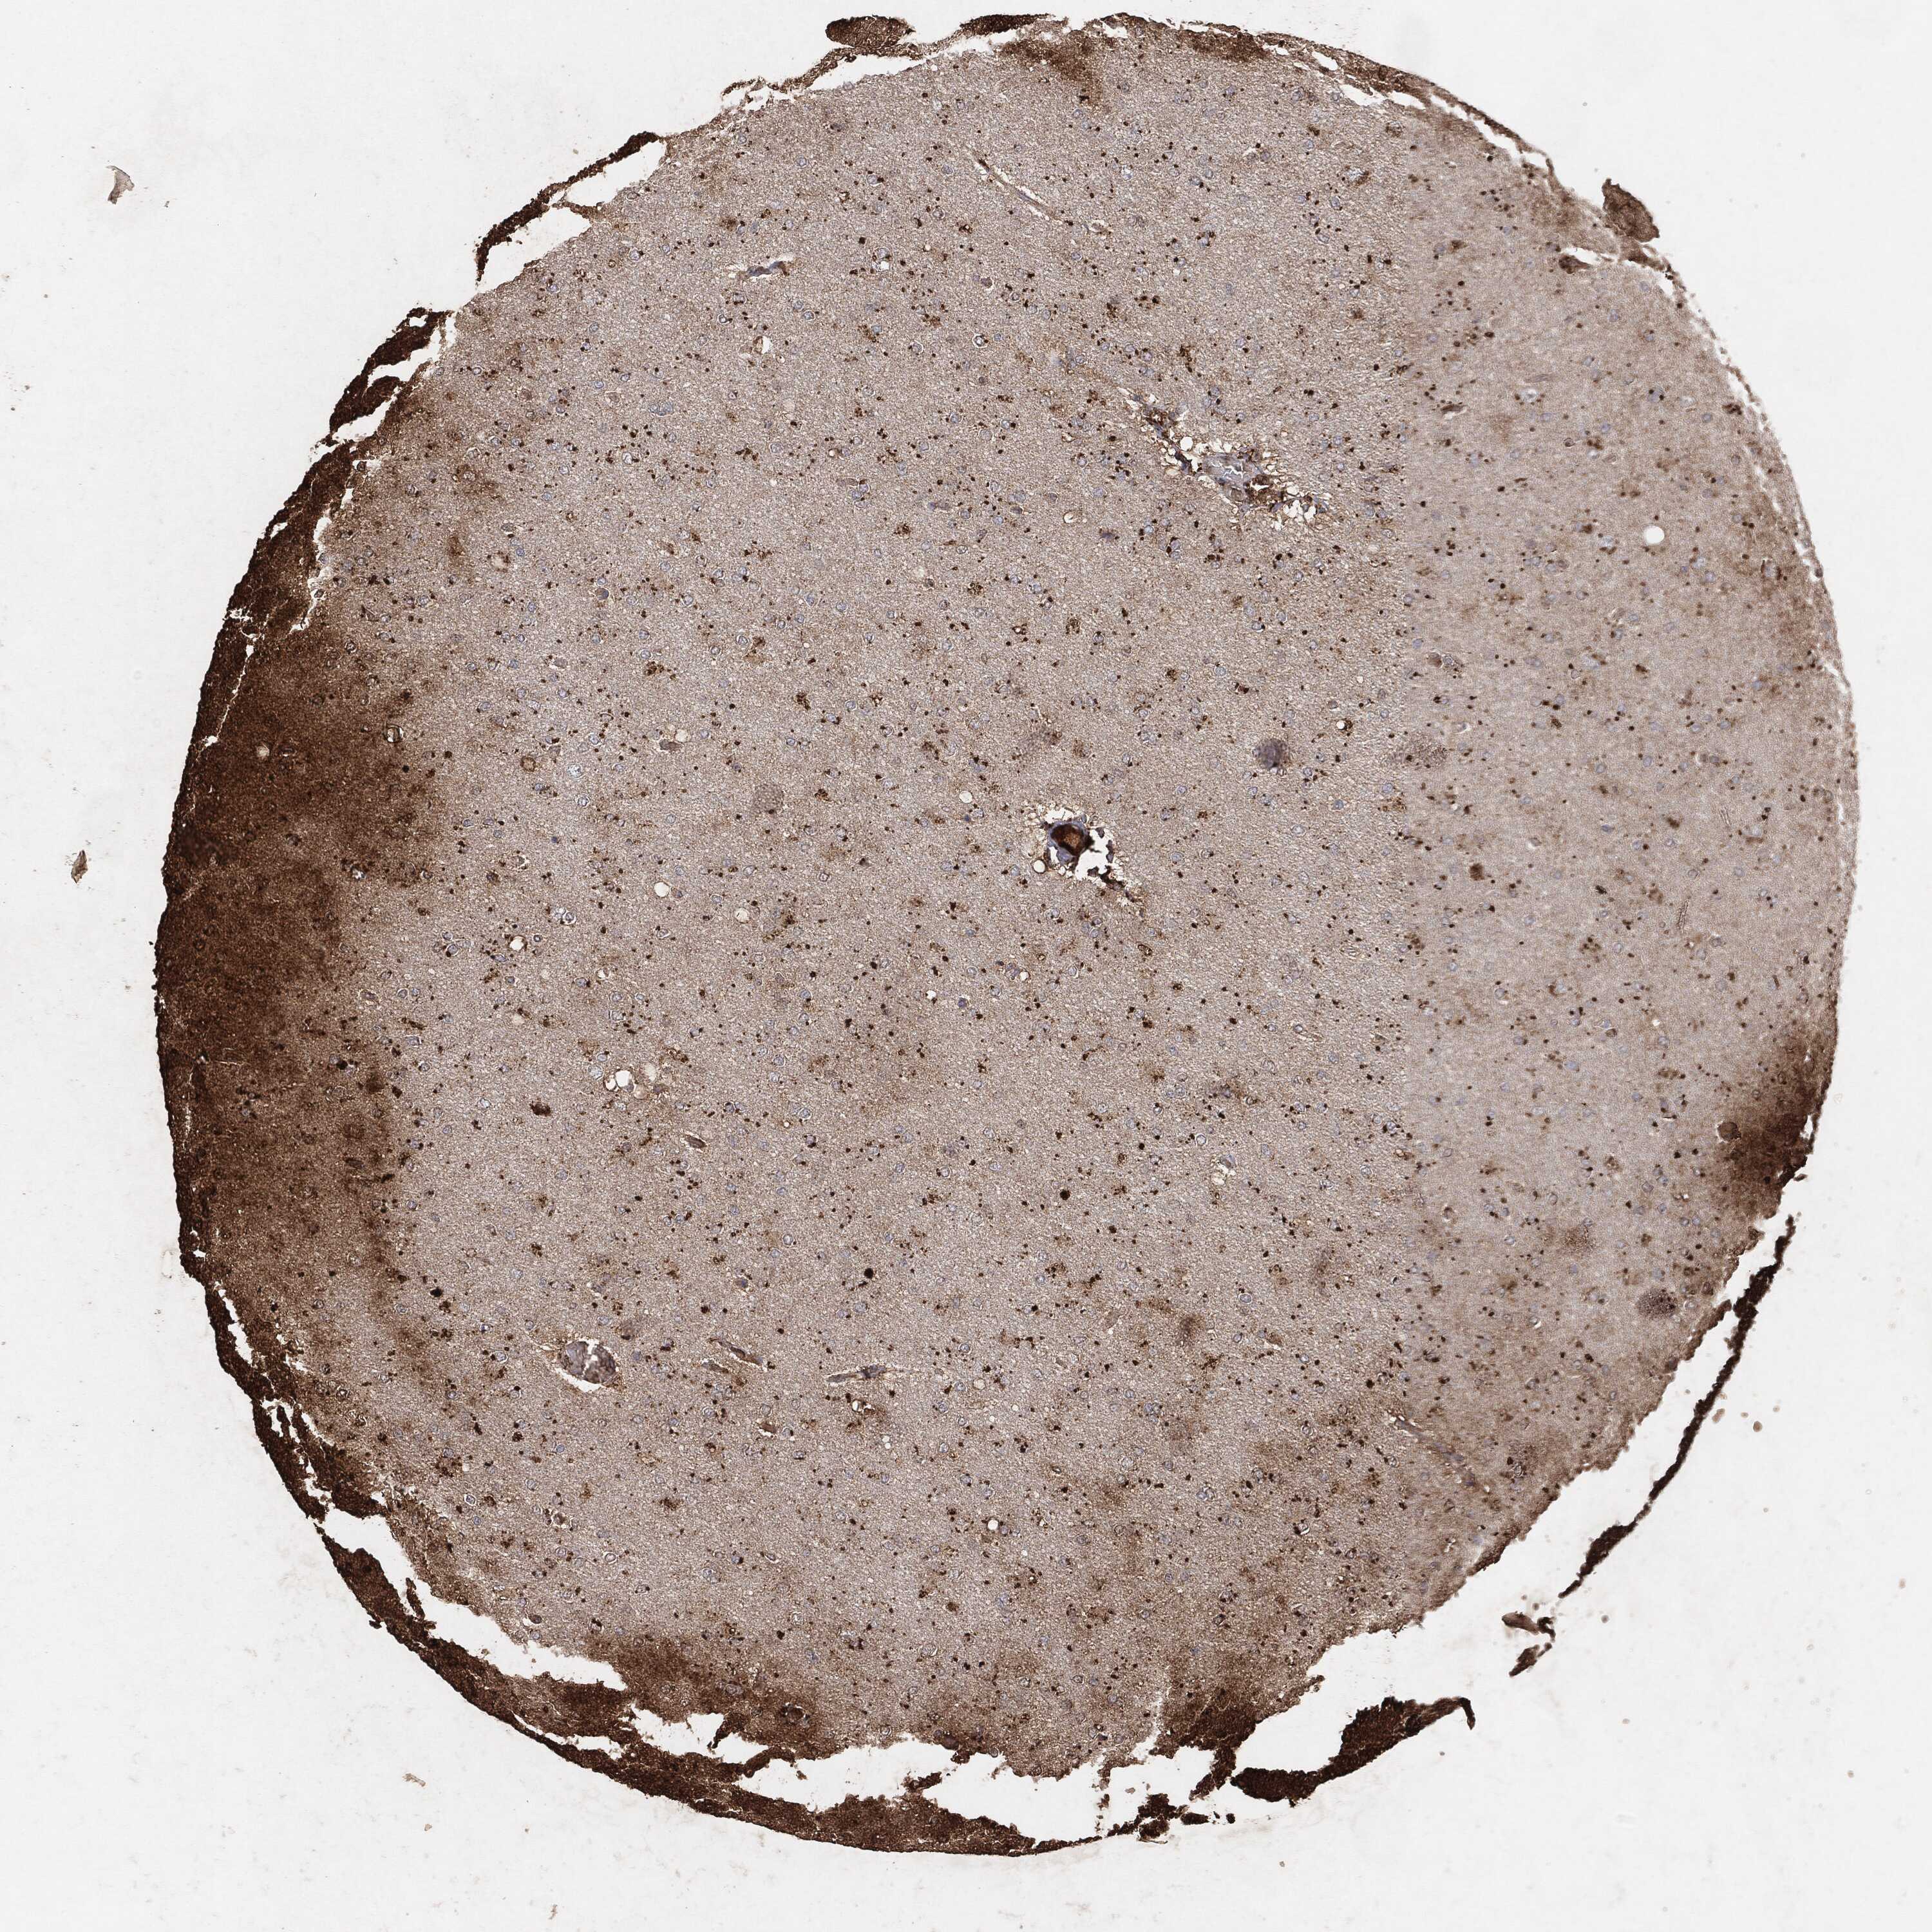

GLIOMA - Protein expressioni

A mouse-over function shows sample information and annotation data. Click on an image to view it in a full screen mode. Samples can be filtered based on level of antibody staining by selecting one or several of the following categories: high, medium, low and not detected. The assay and annotation is described here.

Note that samples used for immunohistochemistry by the Human Protein Atlas do not correspond to samples in the TCGA dataset.

Antibody stainingi

Antibody staining in the annotated cell types in the current human tissue is reported as not detected, low, medium, or high, based on conventional immunohistochemistry profiling in selected tissues. This score is based on the combination of the staining intensity and fraction of stained cells.

Each image is clickable and will lead to virtual microscopy that enables deeper exploration of all samples and also displays staining intensity scores, fraction scores and subcellular localization as well as patient and tissue information for each sample.

Glioma, malignant, High grade

Glioma, malignant, Low grade

Glioma, malignant, NOS